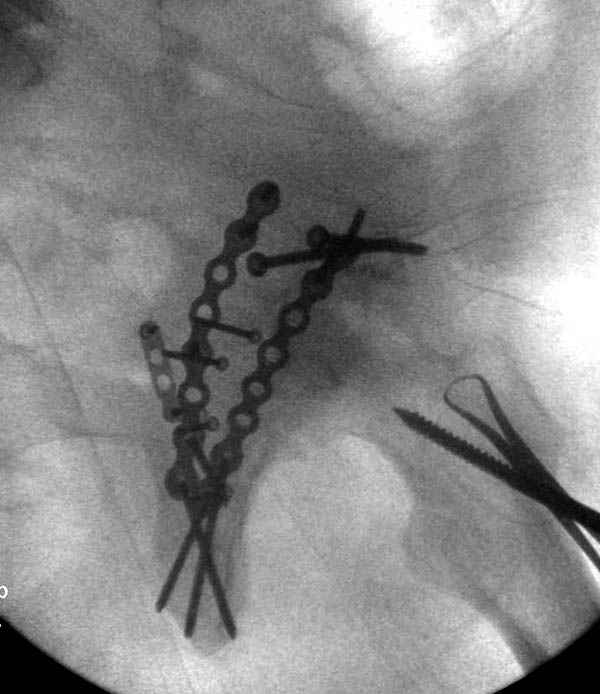

Второй случай, для лечения перелома проксимального

плеча применили пластину "Hand Innovation"

http://www.handinnovations.com/pdf/S3_technique.pdf

Пластина имеет преимущества перед другими "Locking

Implants", потому что пластину можно уложить намного ниже чем другие пластины и имеется возможности проведения шурупов под 130 градусным углом, таким образом можно уменьшить операционный разрез в проксимальной части.

Прооперирован вчера на 13 день после поступления.

Больному 41 и из-за гемодинамической нестабильности в течение первых 7 дней был в реанимации под интубационной седацией.